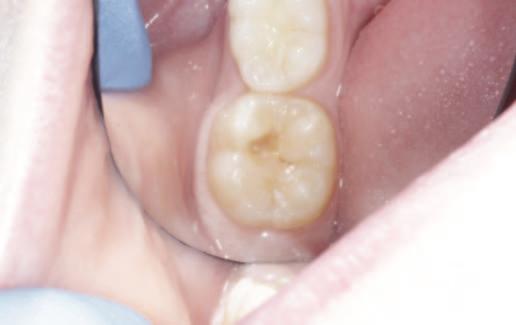

A sagittal split osteotomy approach for removal of a large cementoblastoma at the mandibular angle M. Cotter, Z.G. Khattak, C. Cotter 36